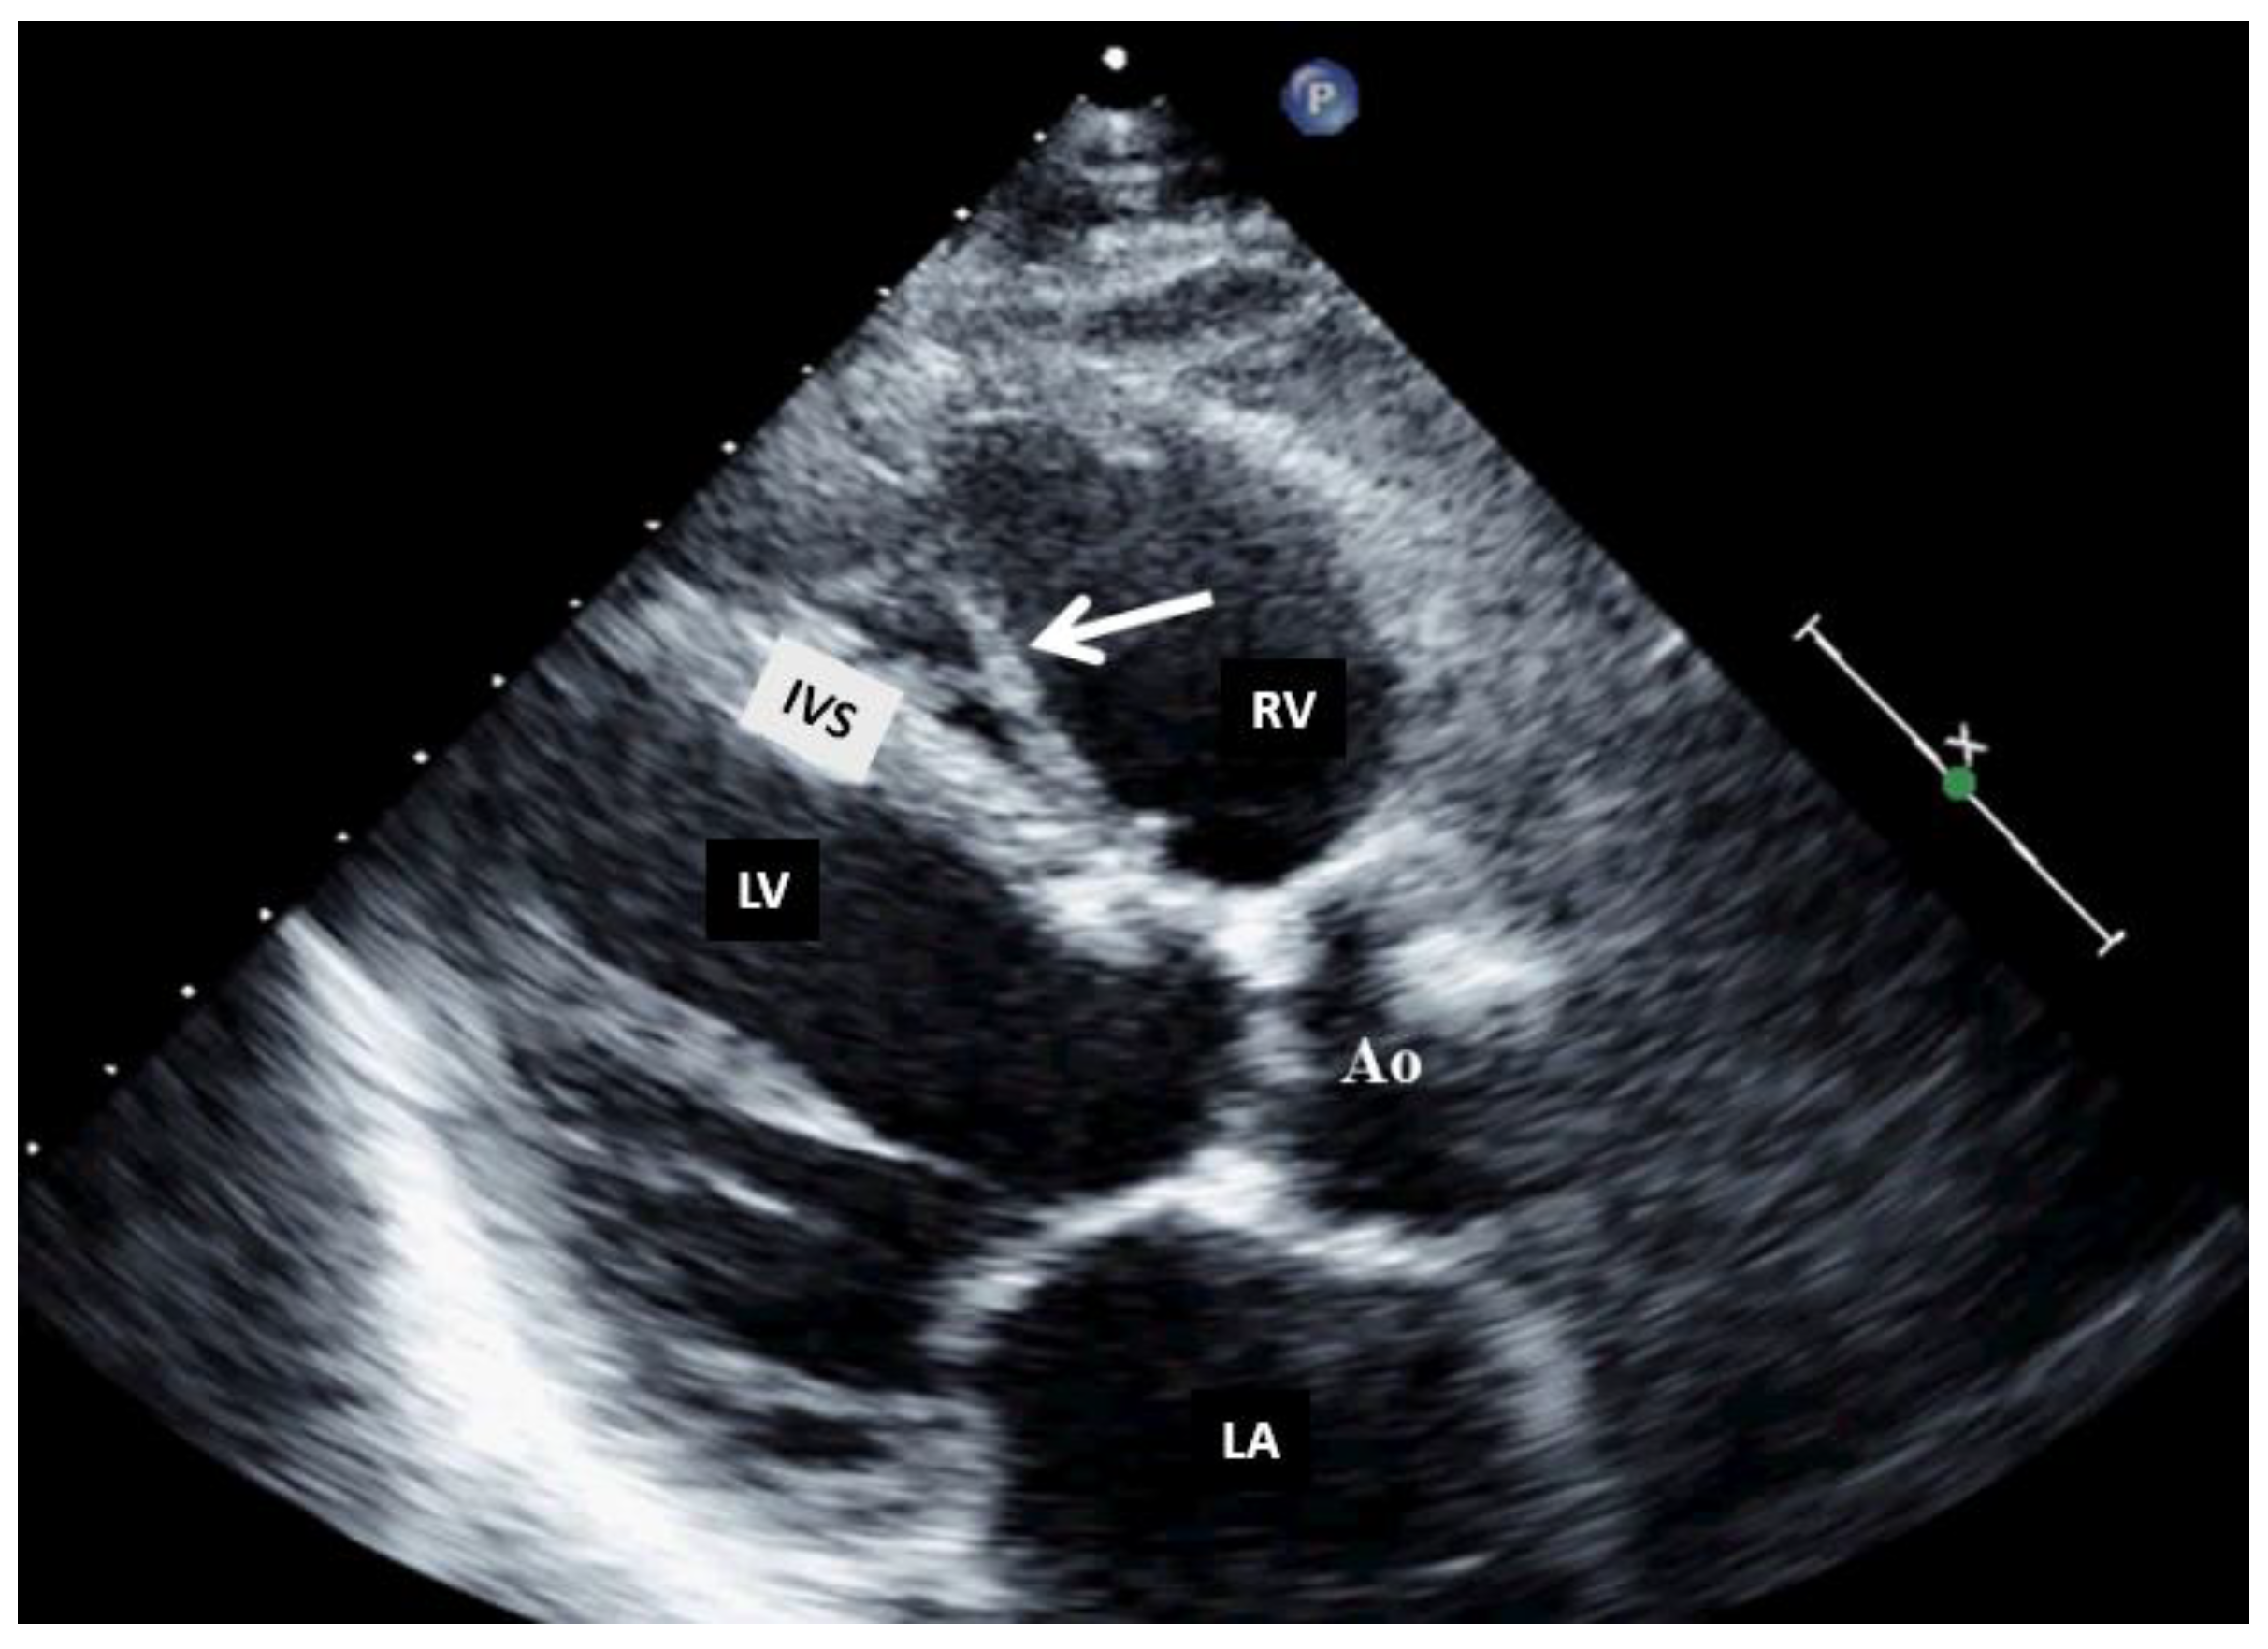

Figure 4. Bi-dimensional transthoracic echocardiography (modified parasternal view long axis) showing moderator band in the right ventricle. AO, aorta; IVS, interventricular septum; LA, left atrium; LV, left ventricle; RV, right ventricle.